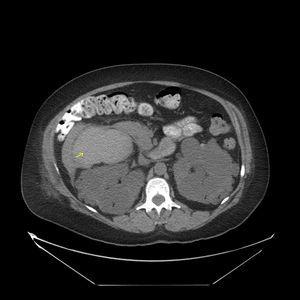

Se solicitó la realización de una ecografía urgente en la que se detectó que hígado y ambos riñones presentaban múltiples formaciones quísticas, pero no se describieron lesiones indicativas de quistes complicados (figura 1). En principio se interpretó el cuadro como una agudización de su insuficiencia renal crónica secundaria a una situación funcional, y se contempló la posibilidad de que existiera una infección quística. Se pautó sueroterapia y un antibiótico (ciprofloxacino), aunque el resultado del urocultivo recibido a los 4 días fue negativo. En las primeras 48 horas desde el ingreso mejoró progresivamente su función renal, pero tras una semana de ingreso la paciente sufre un deterioro brusco de su estado general, anemización con caída del hematocrito de 12 puntos y de la hemoglobina de 4 g/dl (Hb 7,4 g/dl, Hto 21%), caída tensional (TA 93/58 mmHg) y taquicardia (91 sístoles). En un segundo análisis de orina se objetivó una microhematuria solicitándose una segunda ecografía abdominal, hallándose  hematoma intraquístico en la región anterior y en el polo superior del riñón derecho (figura 2). Se completó el estudio mediante una tomografía computarizada abdomino-pélvica sin contraste intravenoso, que confirmó la existencia de una hemorragia intraquística y descartando la presencia de un sangrado retroperitoneal (figura 3 A y figura 3 B).

Figura 3 A. Tomografía computarizada abdómino-pélvica con contraste oral y sin contraste intravenoso.

Figura 3 B. Tomografía computarizada abdominal.